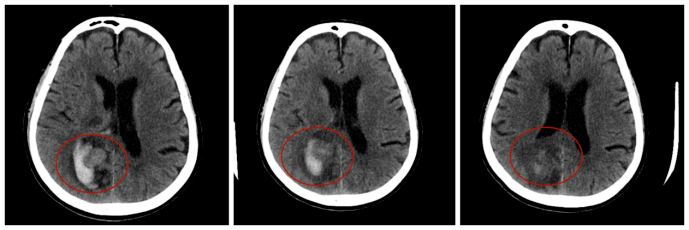

79岁的欧大爷在家中不慎摔倒后突发急性脑梗塞,短短1天内病情急转直下,出现脑梗死出血转化。莆田福德医院神经内科团队迅速启动多学科会诊,通过精准的影像评估、个体化的诊疗方案,成功将欧大爷从危险边缘拉回。如今,他不仅能下地行走,更重拾了与家人共享天伦的幸福时光。这例精准救治案例,正是福德医院神经内科“专业、高效、人文”医疗理念的生动诠释。